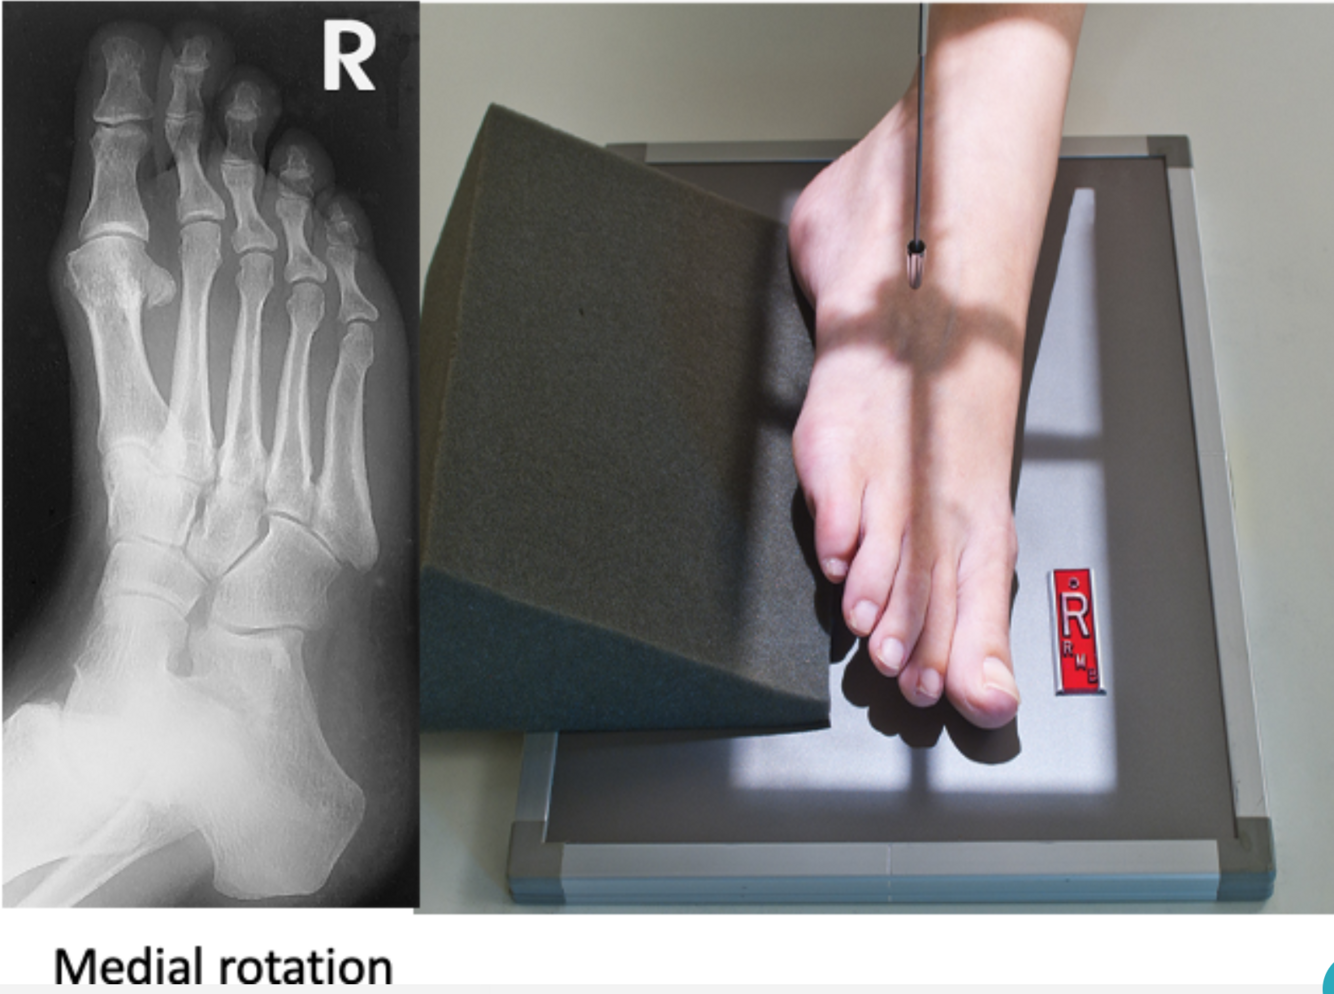

Oblique Foot

A

• IR 10x12 portrait, 40 SID

• Pt supine or sitting, flex knee with plantar surface on table with body turned slightly away from side of injury. Align and center ling axis of foot to CR & long axis of IR. Rotate foot medially to place plantar surface 30-40º to plane of IR. The general plane of the dorsal surface of foot should be parallel to IR & perpendicular to CR. Use sandbags or sponge for support if necessary

• CR perpendicular to 3rd MT base. Collimate to outer margins of ST on 4 sides (approx. 1” each side)